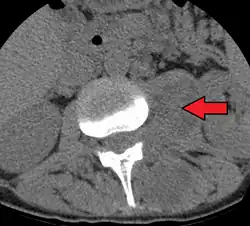

| Paraspinal abscess in the psoas muscle | |

Psoas abscess is a collection of pus (abscess) in the iliopsoas muscle compartment.[1][2][3] It can be classified into primary psoas abscess (caused by hematogenous or lymphatic spread of a pathogen) and secondary psoas abscess (resulting from contiguous spread from an adjacent infectious focus).[3]